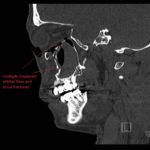

Physical exam showed marked left palpebral subcutaneous crepitus, as well as bulbar and palpebral conjunctival bulging. Visual acuity was normal with intact extraocular movements, and normal pupillary exam. Computed tomography (CT) imaging of the face was obtained and revealed multiple displaced fractures involving the left orbital floor and zygomatic arch associated with moderate periorbital and postseptal extraconal gas, resulting in orbital proptosis.